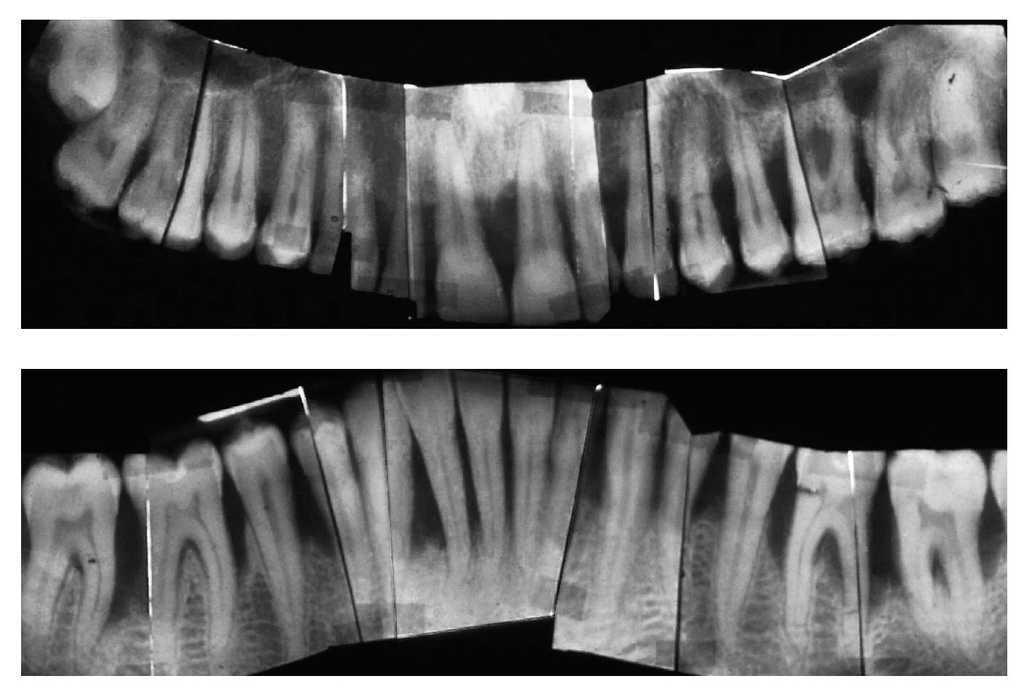

La bibliografía ofrece evidencias de un pronóstico en general muy favorable de los dientes tratados de lesión periodontal. Los datos de una gran cantidad de estudios insisten con vehemencia en la importancia del TPA para la conservación a largo plazo de las estructuras periodontales anteriormente dañadas. El tipo inicial de periodontitis que dio lugar al cuadro clínico no parece desempeñar un papel preponderante en el establecimiento del pronóstico (figs. 1a a 1e).

Figura 1a. Situación periodontal de un paciente de 28 años de edad no fumador en el año 1995.

Figura 1b. Radiografía panorámica en la que el periodoncista ha marcado las piezas dentales con un pronóstico muy desfavorable: 24, 26, 36, 41, 42, 46 y 47.

Figura 1c. Serie de radiografías periapicales tomadas en 1996.

Figura 1d. Situación periodontal del paciente no fumador a los 38 años de edad (año 2005). Reevaluación de las profundidades de sondaje y de la tendencia al sangrado, al principio 3 veces al mes y más tarde de 3 a 4 veces al año, en presencia de una higiene oral excelente.

Figura 1e. La situación periodontal registrada en el año 2006 muestra las profundidades de sondaje residuales y los dientes ausentes, además de la pérdida de inserción y las recesiones aparecidas.